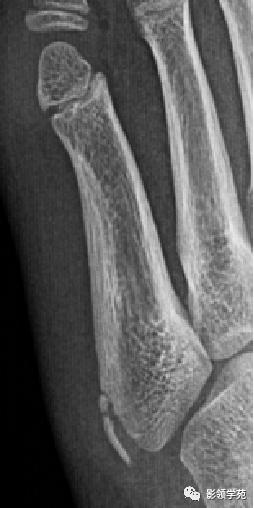

第五跖骨基底部骨折,常为横行骨折,即骨折线垂直于跖骨骨干,它是由于腓侧短肌肌腱应力所引起的撕脱骨折,也称“JONES骨折”。该骨折应与第五跖骨粗隆突起鉴别,尤其是9-15岁的儿童,常常可以出现第五跖骨基底部的骨骺,常表现为纵行透亮线,骨片边缘一般规则光滑,周围软组织无明显肿胀。

第五跖骨粗隆存在独立的骨化中心,并且可有一个或多个骨化中心,常见于10~15岁儿童。一般25岁左右与第五跖骨其余部分融合。

我们所常见的第五跖骨基底部骨折的骨折线一般都是垂直于长轴的,平行于第五跖骨长轴的骨折非常罕见。从外力方向、方式来发现,很难使第五跖骨基底部发生纵形骨折,而该处确实存在骨骺,大量的误诊就是把骨骺当骨折。